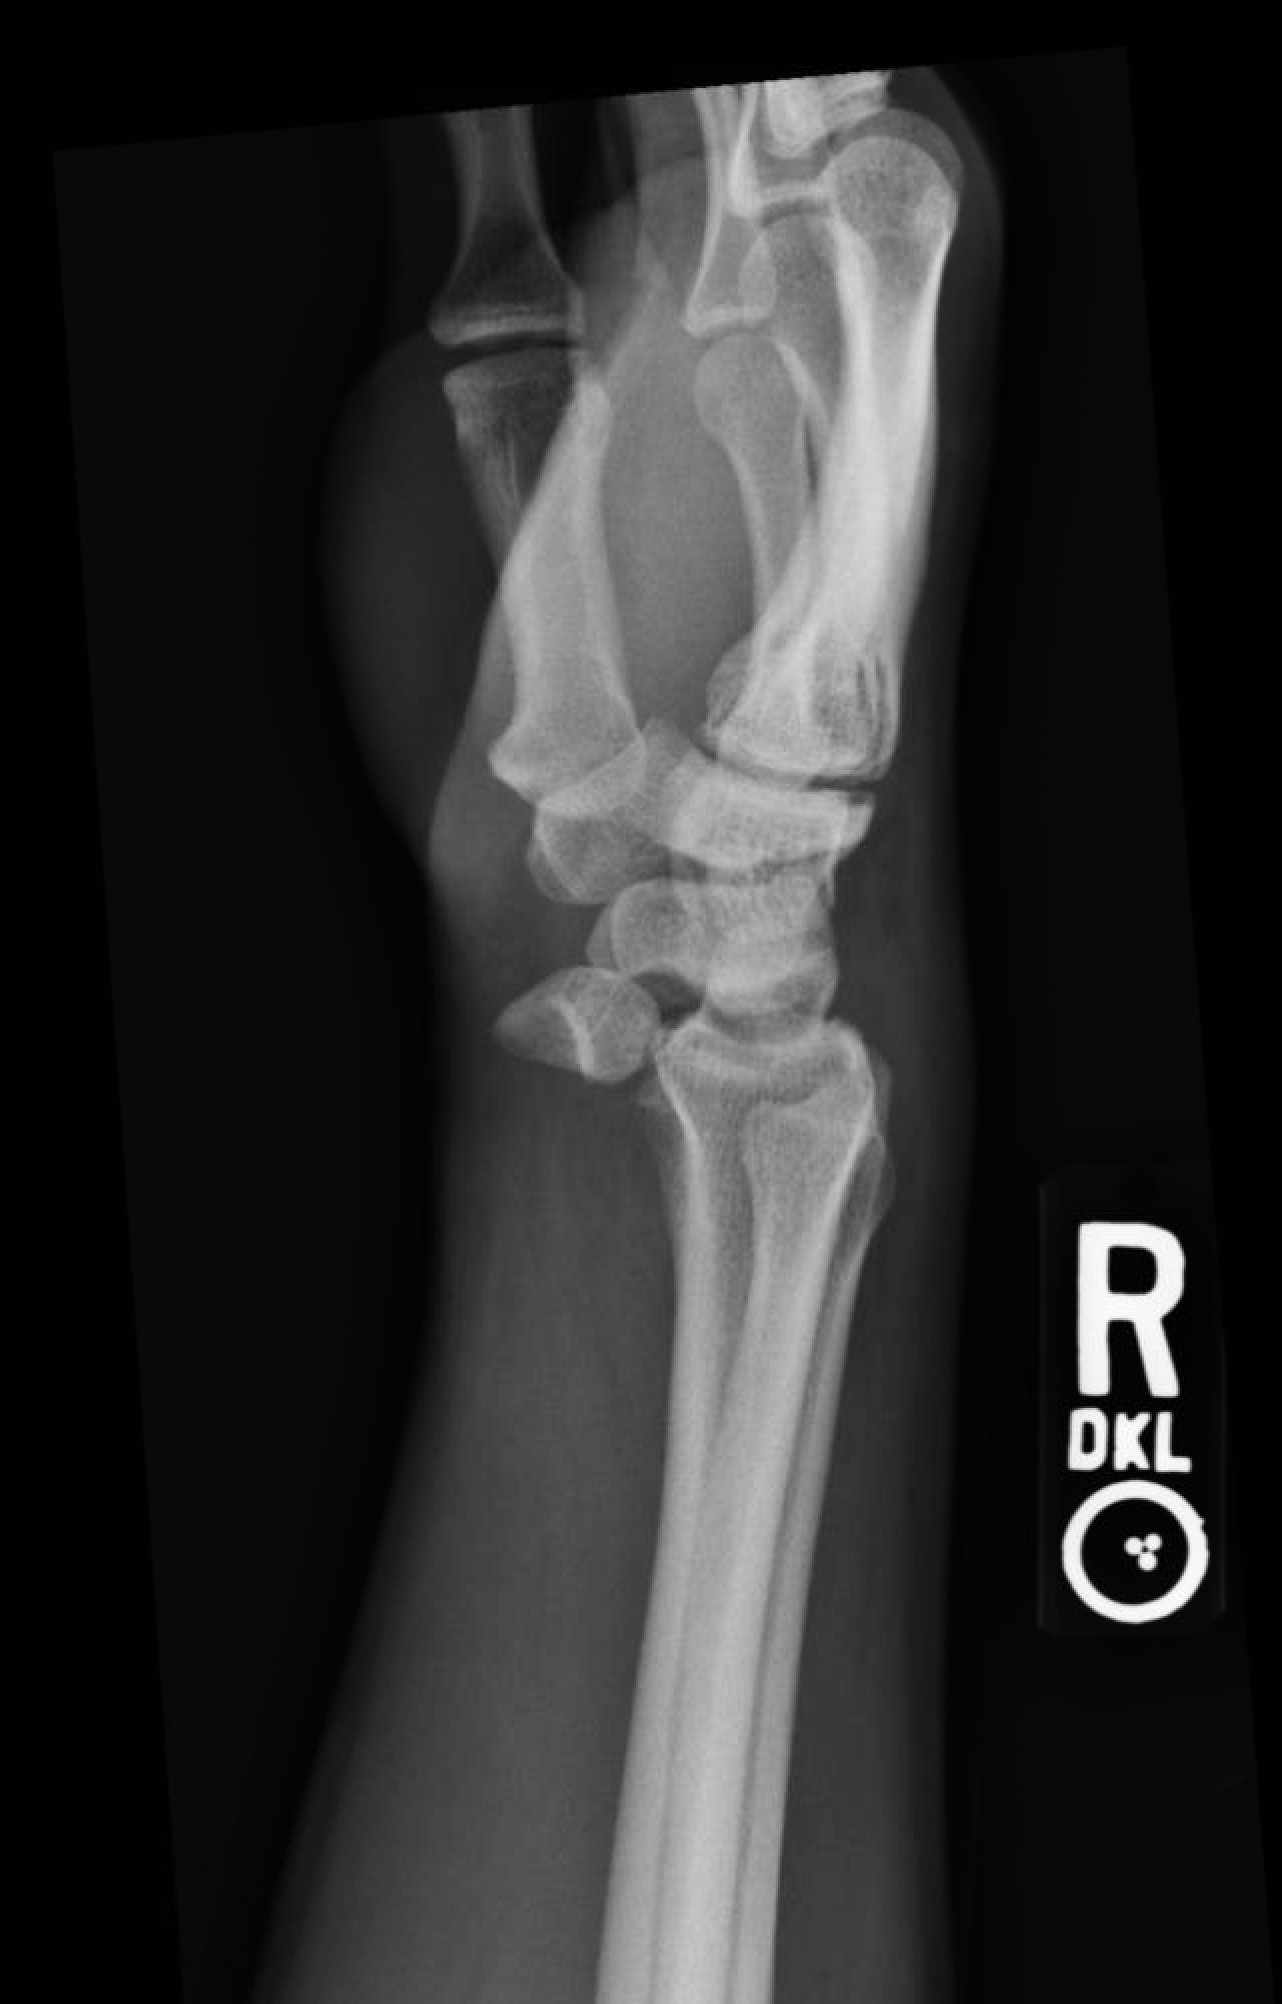

Plain film of the right wrist showed the classic “spilled teacup” consistent with a lunate dislocation. There is a loss of the normal articulation between the distal radius and lunate (white curved highlights represent expected points of articulation).

The most common mechanism leading to a dislocation of lunate is a fall onto an outstretched hand with the wrist in extension. Damage to the ligamentous infrastructure (commonly the dorsal radiolunate ligament) causes destabilization.1 Lunate dislocations are distinguished from perilunate dislocations by assessing for the preservation of the articulation between the lunate and distal radius. In lunate dislocations, this articulation is disrupted leading to the classic “spilled teacup” appearance as seen above. However, if the articulation between the distal radius and lunate is preserved, but there is displacement of the carpal bones (eg, scaphoid, triquetrum, etc), then the dislocation is referred to as a perilunate dislocation.

Plain film radiography oriented in the lateral view is typically the first-line modality for diagnosis. However, advanced imaging such as computed tomography or magnetic resonance imaging may be required to rule out fracture.